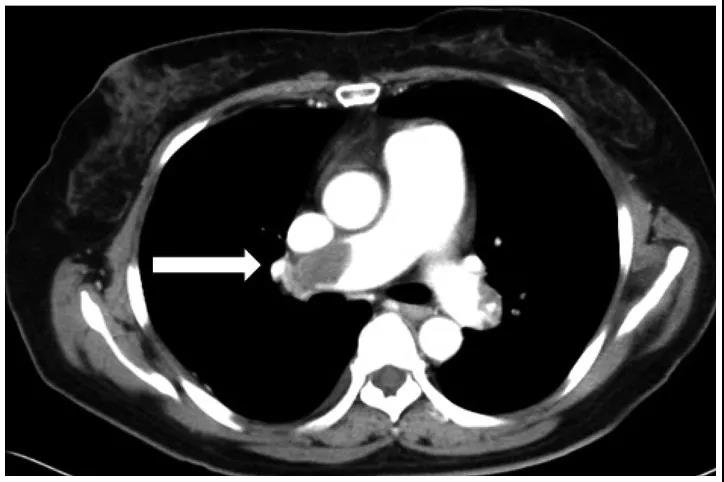

肿瘤急症

有一些肿瘤的急症,可以在短时间内危及患者的生命,例如支气管肺鳞癌导致的大咯血,会使患者被气管内迅速涌出的血液窒息死亡;呕吐、厌食会导致患者出现致死性低钾血症;肿瘤转移至心包则会造成心包填塞,迅速威胁患者生命。另外,恶性肿瘤患者还普遍存在血液高凝情况,是血栓的高危患者,一旦血栓脱落堵塞肺动脉,会引起急性肺栓塞,危及生命。

灰色为血栓